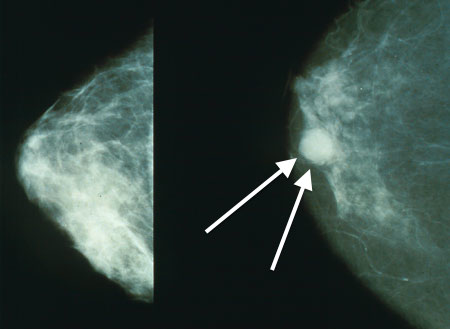

اغلب سرطان های پستان قبل از اینکه احساس شوند و پیش از بروز علائم، در ماموگرافی غربالگری پستان در مراحل اولیه تشخیص داده می شوند.

توجه داشته باشید که آزمایش های غربالگری و ماموگرافی کمک می کنند تا قبل از بروز هر گونه علائم، سرطان پستان را هر چه سریع تر کشف کنید و شانس بیشتری برای درمان داشته باشید.

ماموگرام

بیوپسی یا نمونه برداری هنگامی انجام می شود که ماموگرافی، سایر آزمایش های تصویربرداری یا معاینات فیزیکی تغییراتی در پستان را نشان دهند. بیوپسی تنها راه مطمئنی است که نشان می دهد آیا سرطان دارید یا نه.

البته توجه داشته باشید که برخی اوقات، از هیچ گونه علائم ظاهری خبری نیست و تنها انجام آزمایش های غربالگری پستان و ماموگرافی در کلینیک غربالگری سرطان پستان می تواند شما را از وجود آن آگاه سازد.